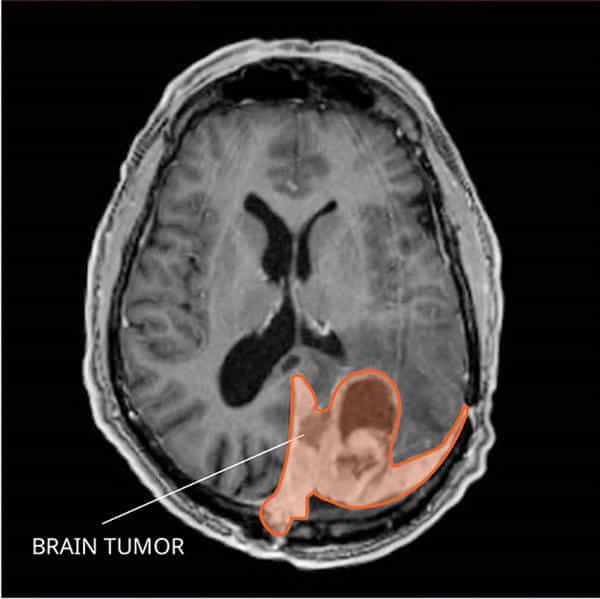

Imaging Tests

Imaging tests such as magnetic resonance imaging (MRI) and computed tomography (CT) scans are essential in diagnosing meningioma. These tests provide detailed images of the brain and spinal cord, allowing the healthcare team to locate and evaluate the tumor. In some cases, additional imaging tests such as angiography or positron emission tomography (PET) scans may be performed to gather more information about the tumor’s characteristics and blood supply.